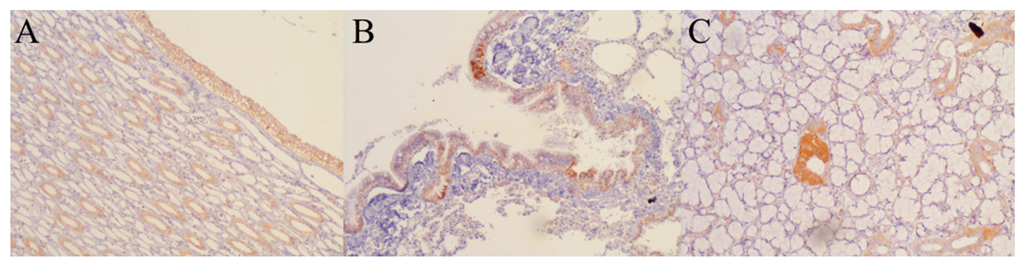

3.4. Early Biodistribution Is Not Widespread

| Tissue | RT-PCR | IHC | Tissue | RT-PCR | IHC |

|---|---|---|---|---|---|

| Kidney | + | + | Pancreas | − | − |

| Salivary gland | + | + | Adipose tissue | − | − |

| Stomach | + | − | Colon | − | − |

| Lung | − | + | Brain | − | − |

| Cancerous tissues | − | − | Cerebelum | − | − |

| Striated skeletal muscle | − | − | Adrenal gland | − | − |

| Fibroadipose tissue | − | − | Cell package | − | − |

| Nervous package | − | − | Serum | − | − |

| Liver | − | − | Cerebrospinal fluid | − | − |

| Squamous mucosa | − | − |